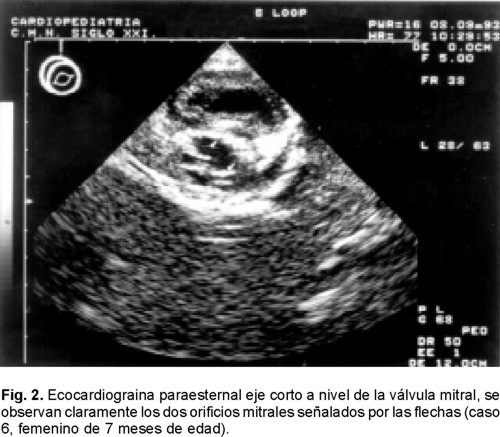

Se encontraron 16 enfermos en un periodo de 10 años (Tabla I). El rango de edad fue de 2 meses a 10 años, media de 3 ± 3.08 años. Diez enfermos fueron masculinos y 6 femeninos. En 7 de los 16 (43%) la obstrucción se debió a fusión de comisuras de las valvas y cuerdas tendinosas en presencia de dos músculos papilares (Fig. 1). En 6 (37%) se encontró válvula mitral en paracaídas, en un enfermo (6%) se documentó la presencia de anillo supravalvular mitral combinado con fusión de las comisuras valvulares, en otro caso se observó fusión directa de los músculos papilares con las valvas por ausencia de cuerdas tendinosas y uno más tenía doble orificio mitral con fusión de comisuras y cuerdas tendinosas (Fig. 2). En ningún enfermo se encontró el síndrome Shone completo, sin embargo, sólo en 2 (12.5%) se encontró la estenosis mitral como lesión aislada.

Reparación mitral quirúrgica. Se efectuó en 6 casos. En el enfermo con diafragma supravalvular mitral y fusión de comisuras (caso 9), la resección del diafragma se hizo al inicio en el borde posterior y terminó en el anterior, separando el diafragma de las valvas y cuidando no dañarlas, luego se efectuó la comisurotomía mitral. En los enfermos con fusión de comisuras y cuerdas tendinosas, (casos 1, 4, 13 y 16), se hizo la comisurotomía combinada con fenestración de las cuerdas y separación de músculos papilares para ampliar el espacio entre las cuerdas y la excursión de las valvas y se resecó el tejido redundante entre las cuerdas. Dos de estos casos, 8 años después requirieron prótesis mitral (casos 4 y 13) (Tabla I). En el enfermo con válvula mitral en paracaídas y doble orificio mitral (caso 12), el músculo papilar único fue separado mediante una incisión en dos: una porción posterior y otra anterior, las cuerdas tendinosas fueron fenestradas y el puente de tejido valvar que producía los dos orificios fue resecado. En combinación con la reparación mitral se cerró una comunicación interventricular en 3 casos, uno de los cuales falleció en la operación al inicio de esta serie (caso l). La implantación de prótesis mitral se llevó a cabo en 4 enfermos, en dos de ellos esto ocurrió 8 años después de la reparación mitral debido a insuficiencia mitral severa, en los otros dos el implante protésico fue primario. Uno de estos casos tenía fusión directa de los músculos papilares a las valvas mitrales, lo que impidió la reparación (caso 7) y en el otro enfermo, (caso 11) la evaluación intraoperatoria después de la comisurotomía valvular, separación de músculos papilares y fenestración de cuerdas, reveló inadecuada coaptación de las valvas provocando insuficiencia mitral importante por lo que se procedió al implante protésico. Las prótesis utilizadas fueron St. Jude 21, Carbomedics 23, St. Jude 25 y St. Jude 25 respectivamente (casos 4, 7, 11 y 13). La derivación cardiopulmonar (DCP) en las reparaciones mitrales fue de 128 ± 16 minutos y el pinzamiento aórtico de 45 ± 12, sin diferencia estadística con relación a los tiempos de implantación de prótesis mitral 118 ± 12 de DCP y 33 ± 11 minutos de pinzamiento aórtico. Los cuatro enfermos con prótesis reciben anticoagulación oral para mantener niveles de INR entre 2.5 y 3.5.